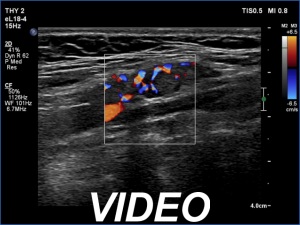

Ultrasonography. There was no thyroid tissue in the thyroid beds. There were moderately hypoechoic lesions next to each other in the left side of the neck. The presentation corresponded to a conglomerate of metastatic lymph nodes.

Cytology resulted in papillary cancer.

The patient was reoperated and multiple lymph nodes were removed from the left side of the neck. Histopathology disclosed metastases of papillary cancer.